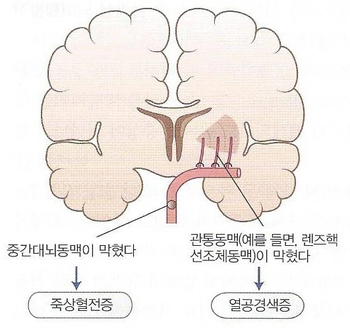

혈전은 비교적 천천히 동맥의 협착과 폐쇄를 일으킵니다. 그리고 어느 정도 두께의 동맥이 폐쇄되느냐에 따라 혈전성 뇌경색과 열공성 뇌경색으로 구분합니다. 전자는 비교적 굵은 동맥(전·중·후대뇌동맥)에 발생하고 후자는 관통동맥(교합혈관이 없는 동맥)에 생깁니다.

혈전의 호발 부위의 신경 증상은 뇌경색 부위와 크기, 그리고 측부 순환 혈액량에 따라 결정됩니다. 혈전이 생기는 호발 부위는 위 그림과 같고 비교적 굵은 뇌동맥이 폐쇄되었을 때의 증상은 아래 표와 같습니다.전대뇌동맥폐쇄치매, 인격변화, 자발성결핍, 이상반사중대뇌동맥폐쇄의식장애, 반신마비, 지각장애, 언어장애후대뇌동맥폐쇄시야장애, 시각인지불능, anton실명